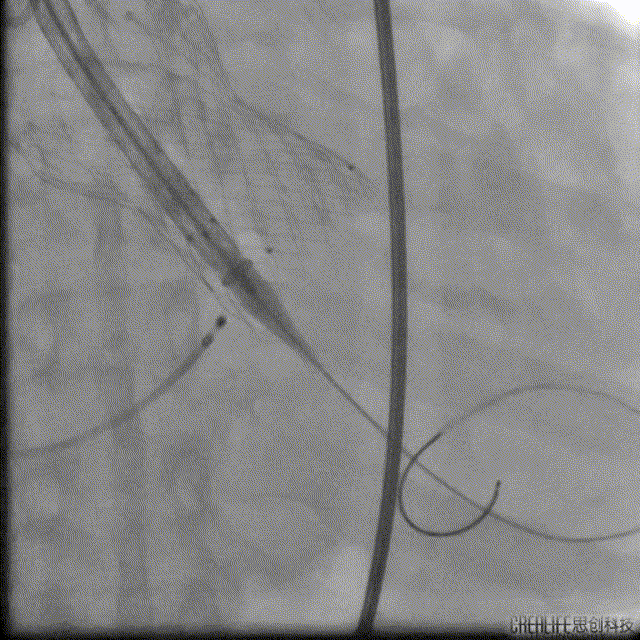

Numed25预扩

Venus32上跳

Venus32回收

VenusAplus32释放

VenusA32瓣膜瓣中瓣